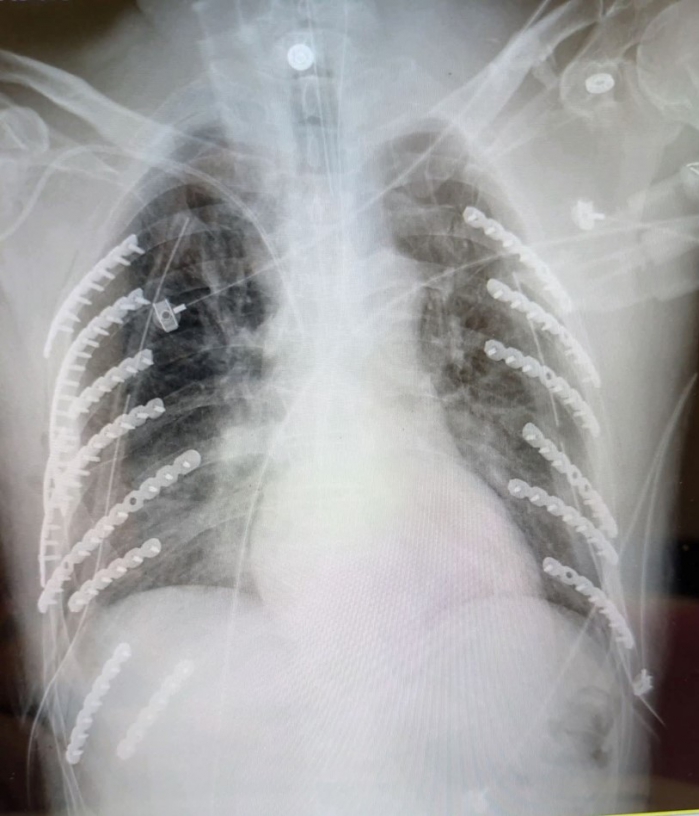

衛生福利部臺中醫院胸腔外科何蕙如醫師表示,患者第一時間被送往最近的急救醫院先插上胸管,確認生命跡象穩定後轉送到院,x光片顯示,雙側同時遭擠壓導致兩側共兩對二十八根肋骨,他就斷了十四根肋骨,甚至一根肋骨斷好幾截,比一般外傷平均斷裂三到五根嚴重許多;另外還合併左側鎖骨及部分脊柱裂傷,以及呼吸衰竭需插氣管內管,病況危急。

幸好斷裂肋骨數量雖多,何蕙如醫師評估肋骨未穿刺血管,在加護病房評估生命跡象穩定後,決定分兩階段手術,第一次植入八根、第二次植入六根鈦合金鋼骨,使肋骨復位固定,術後患者恢復良好,住院三周順利自己走著出院,他還自嘲身上十四根鈦合金,從此變成「鋼鐵人」,跟穿古代金鐘罩一樣厲害。